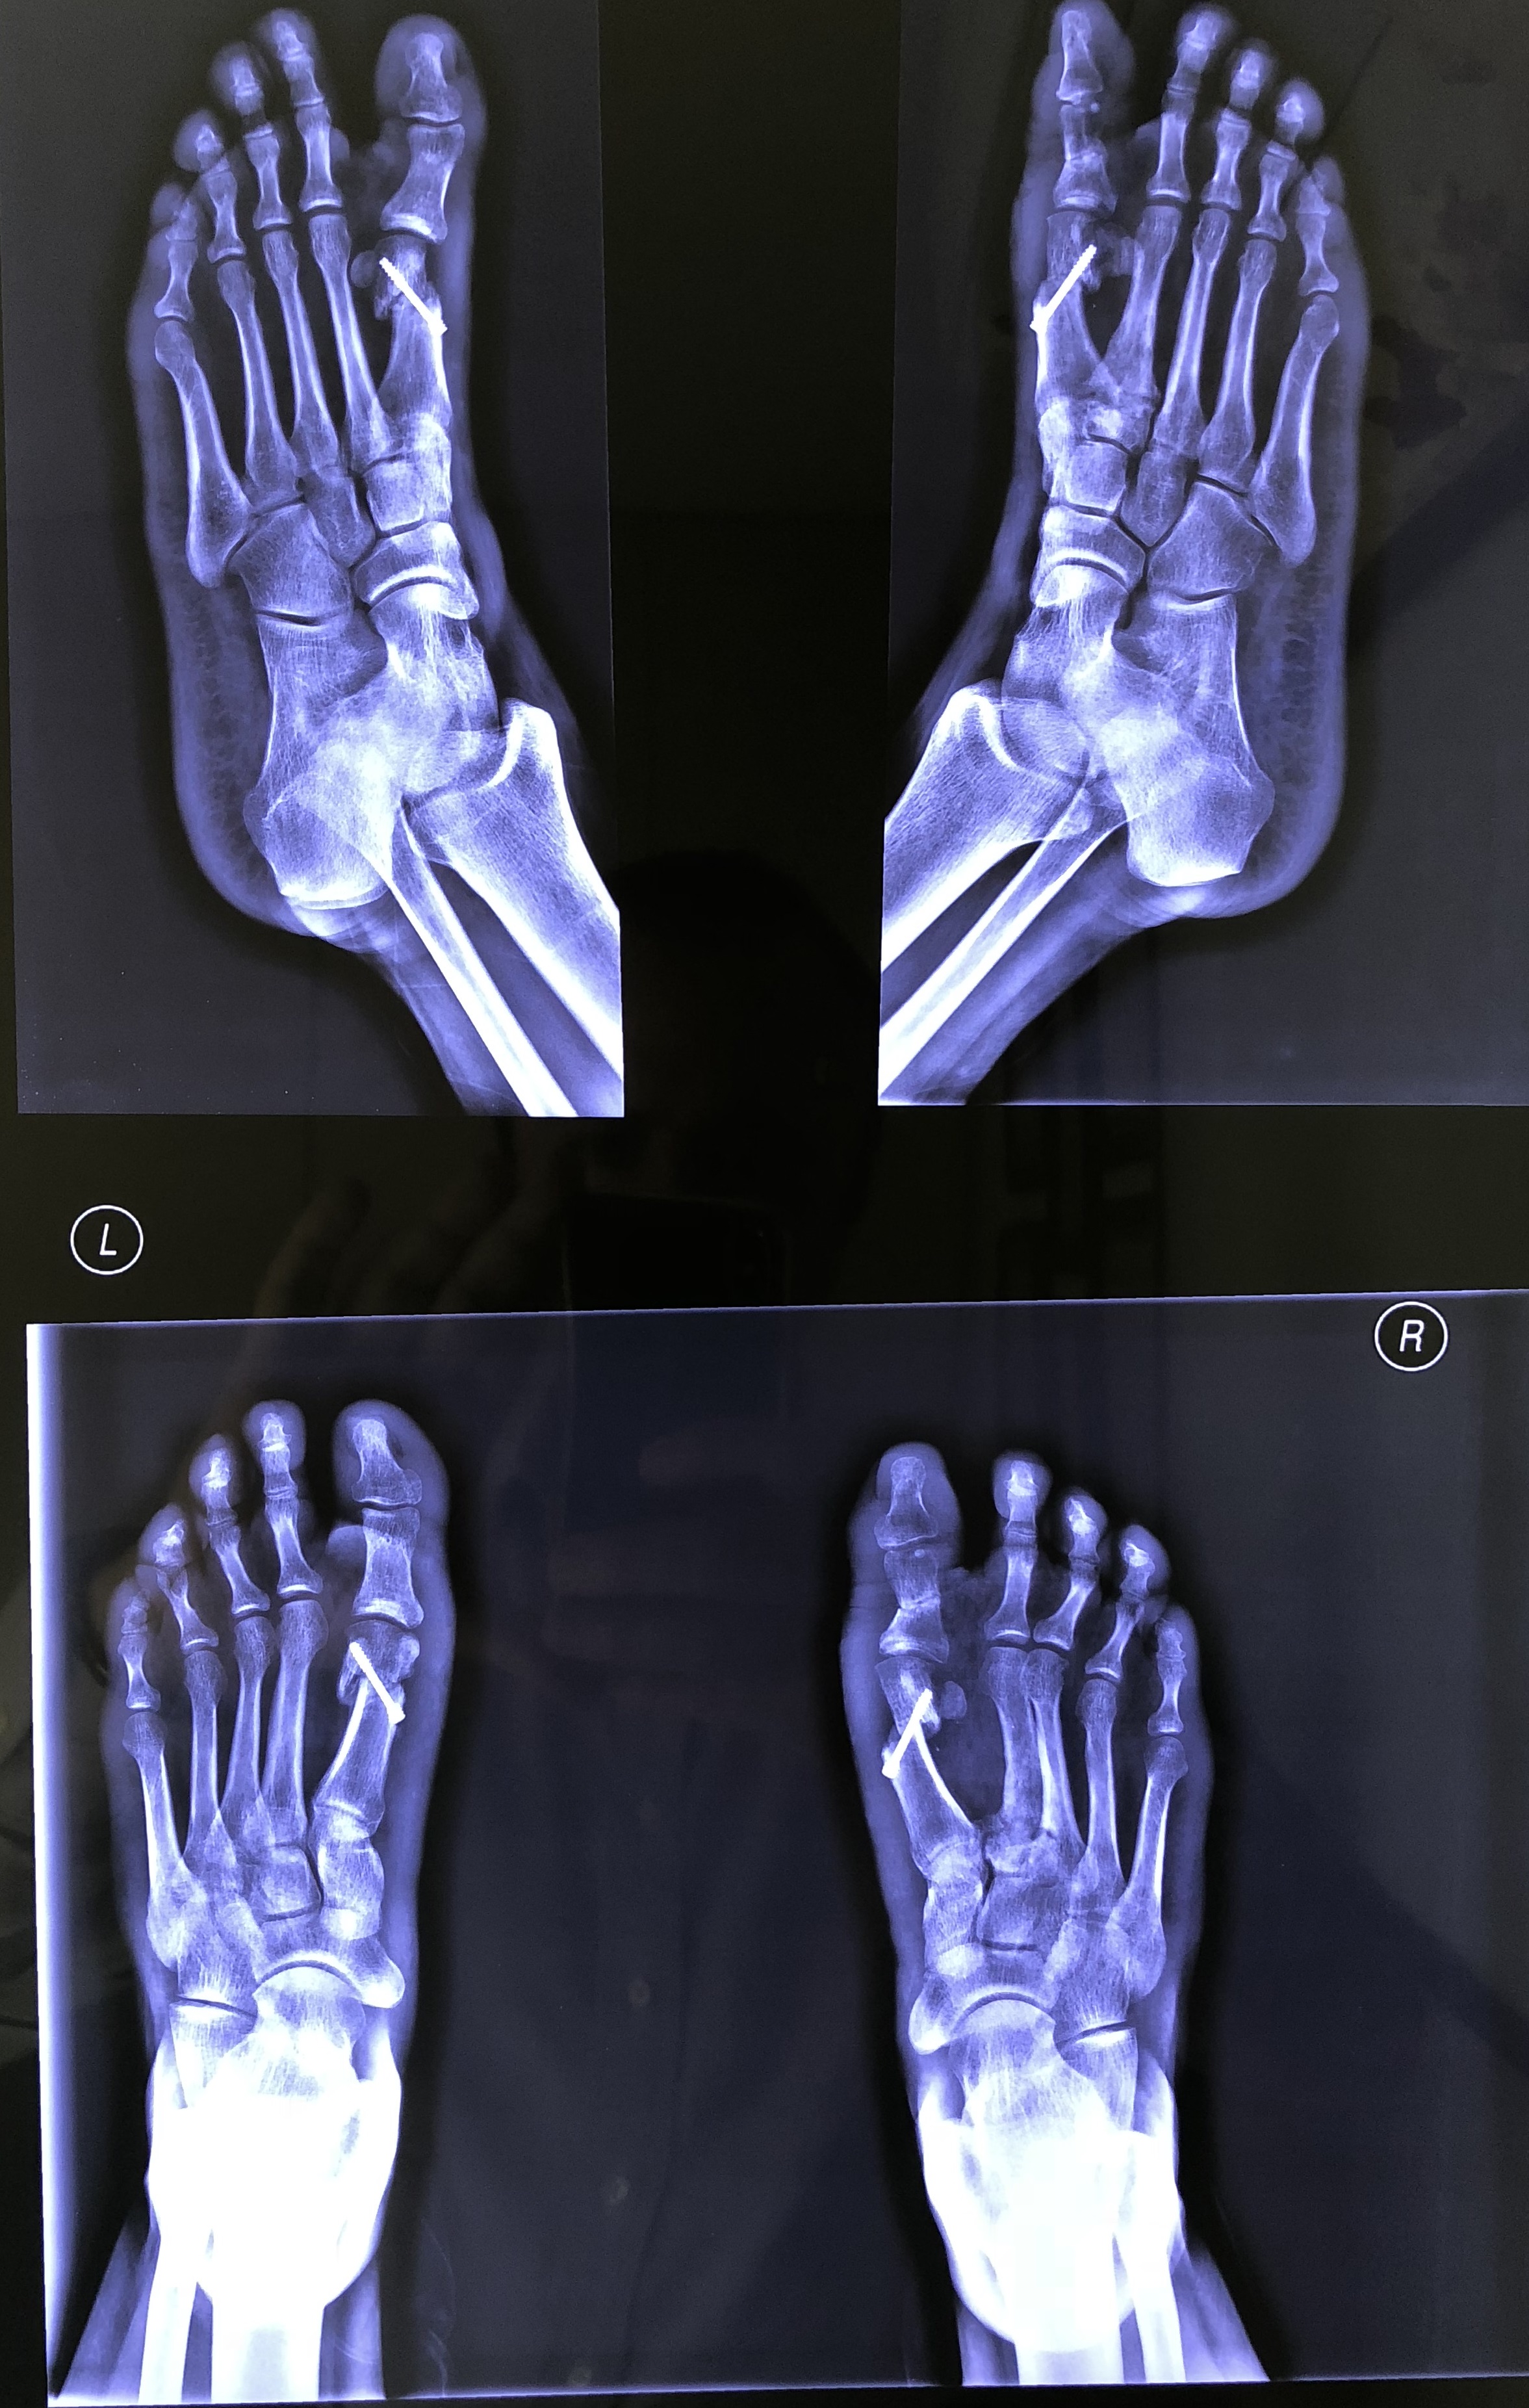

Upload Date: January 21, 2019 Full Size Image Dimensions: 2353 × 3705 Image Parent Post: ΧΕΙΡΟΥΡΓΙΚΗ ΚΑΤΩ ΑΚΡΟΥ

d.Μετεγχειρητικές ακτινογραφίες βλ

• ΔΙΟΡΘΩΣΕΙΣ ΠΑΡΑΜΟΡΦΩΣΕΩΝ ΔΑΚΤΥΛΩΝ ΠΟΔΙΩΝ ΕΛΑΧΙΣΤΗΣ ΕΠΕΜΒΑΤΙΚΟΤΗΤΑΣ

ΔΙΟΡΘΩΣΕΙΣ ΠΑΡΑΜΟΡΦΩΣΕΩΝ ΔΑΚΤΥΛΩΝ ΠΟΔΙΩΝ ΕΛΑΧΙΣΤΗΣ ΕΠΕΜΒΑΤΙΚΟΤΗΤΑΣ

Με την καινούργια αυτή τεχνική ελάχιστης επεμβατικότητας (Minimally Invasive Surgery) η χειρουργική επέμβαση … Διαβάστε περισσότερα